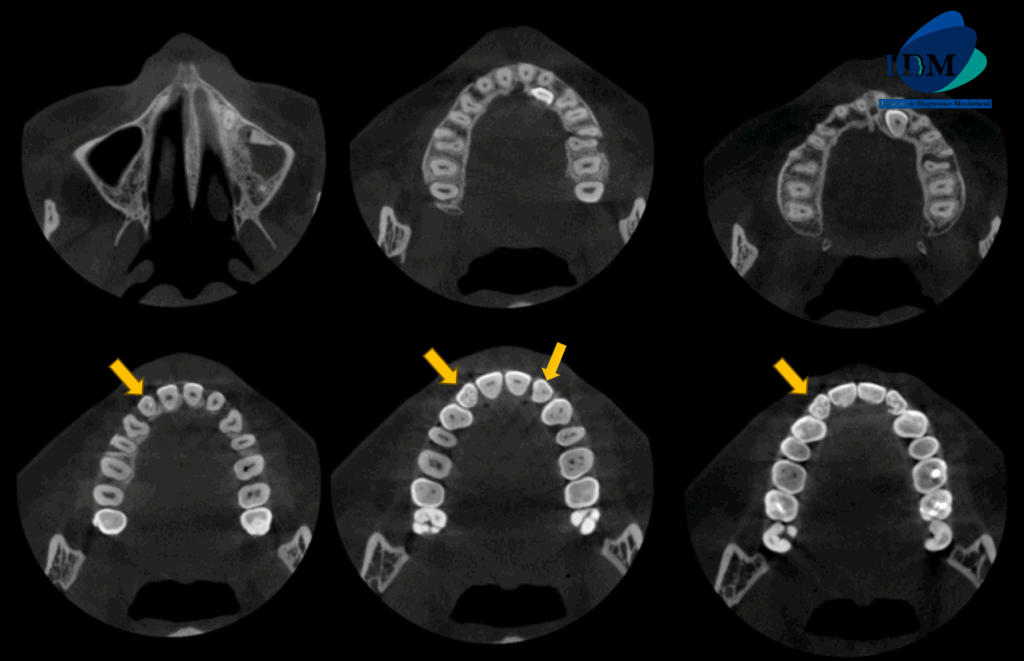

A la evaluación de la tomografía de campo mediano en cortes axiales, transaxiales y tangenciales se evidencia un detalle que en la panorámica paso un poco inadvertida y es que las piezas 12 y 22 presentan una alteración de la morfología coronaria compatible con dientes invaginados.

CORTES AXIALES